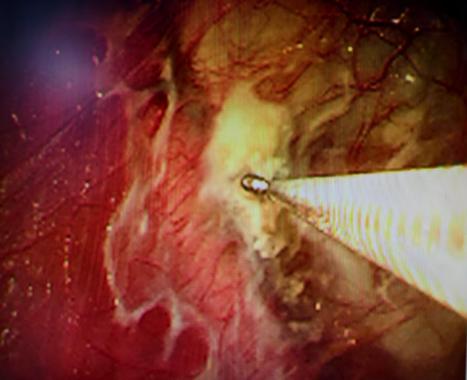

近期,国内知名呼吸介入专家陈愉教授联合做爱自拍 呼吸与危重症医学科团队,为李先生施行“胸腔镜下肺大疱探查术 + 胸腔闭式引流术”。手术中,陈愉教授运用单孔胸腔镜技术,仅在患者胸壁开了一个1cm的小切口。通过高清胸腔镜系统探查发现,患者胸腔内存在广泛粘连以及多发微小肺大疱,肺叶解剖结构异常,肺门血管直接暴露,经判断肺大疱腔已与胸腔贯通。

面对这一复杂状况,陈教授凭借丰富的经验果断调整手术方案。在确保安全的前提下,对可疑病灶进行了精准活检取样,随后精准置入胸腔引流管。术后即刻CT确认引流管位置良好,同时制定了严密的术后管理方案:每日监测引流量及肺复张情况,若引流量持续减少且肺大疱逐渐缩小,则按计划拨管;若肺大疱未明显缩小,则考虑拔除引流管后转外科进行胸膜剥离术。

(胸腔镜下可见胸腔粘连、多个微小肺大疱)